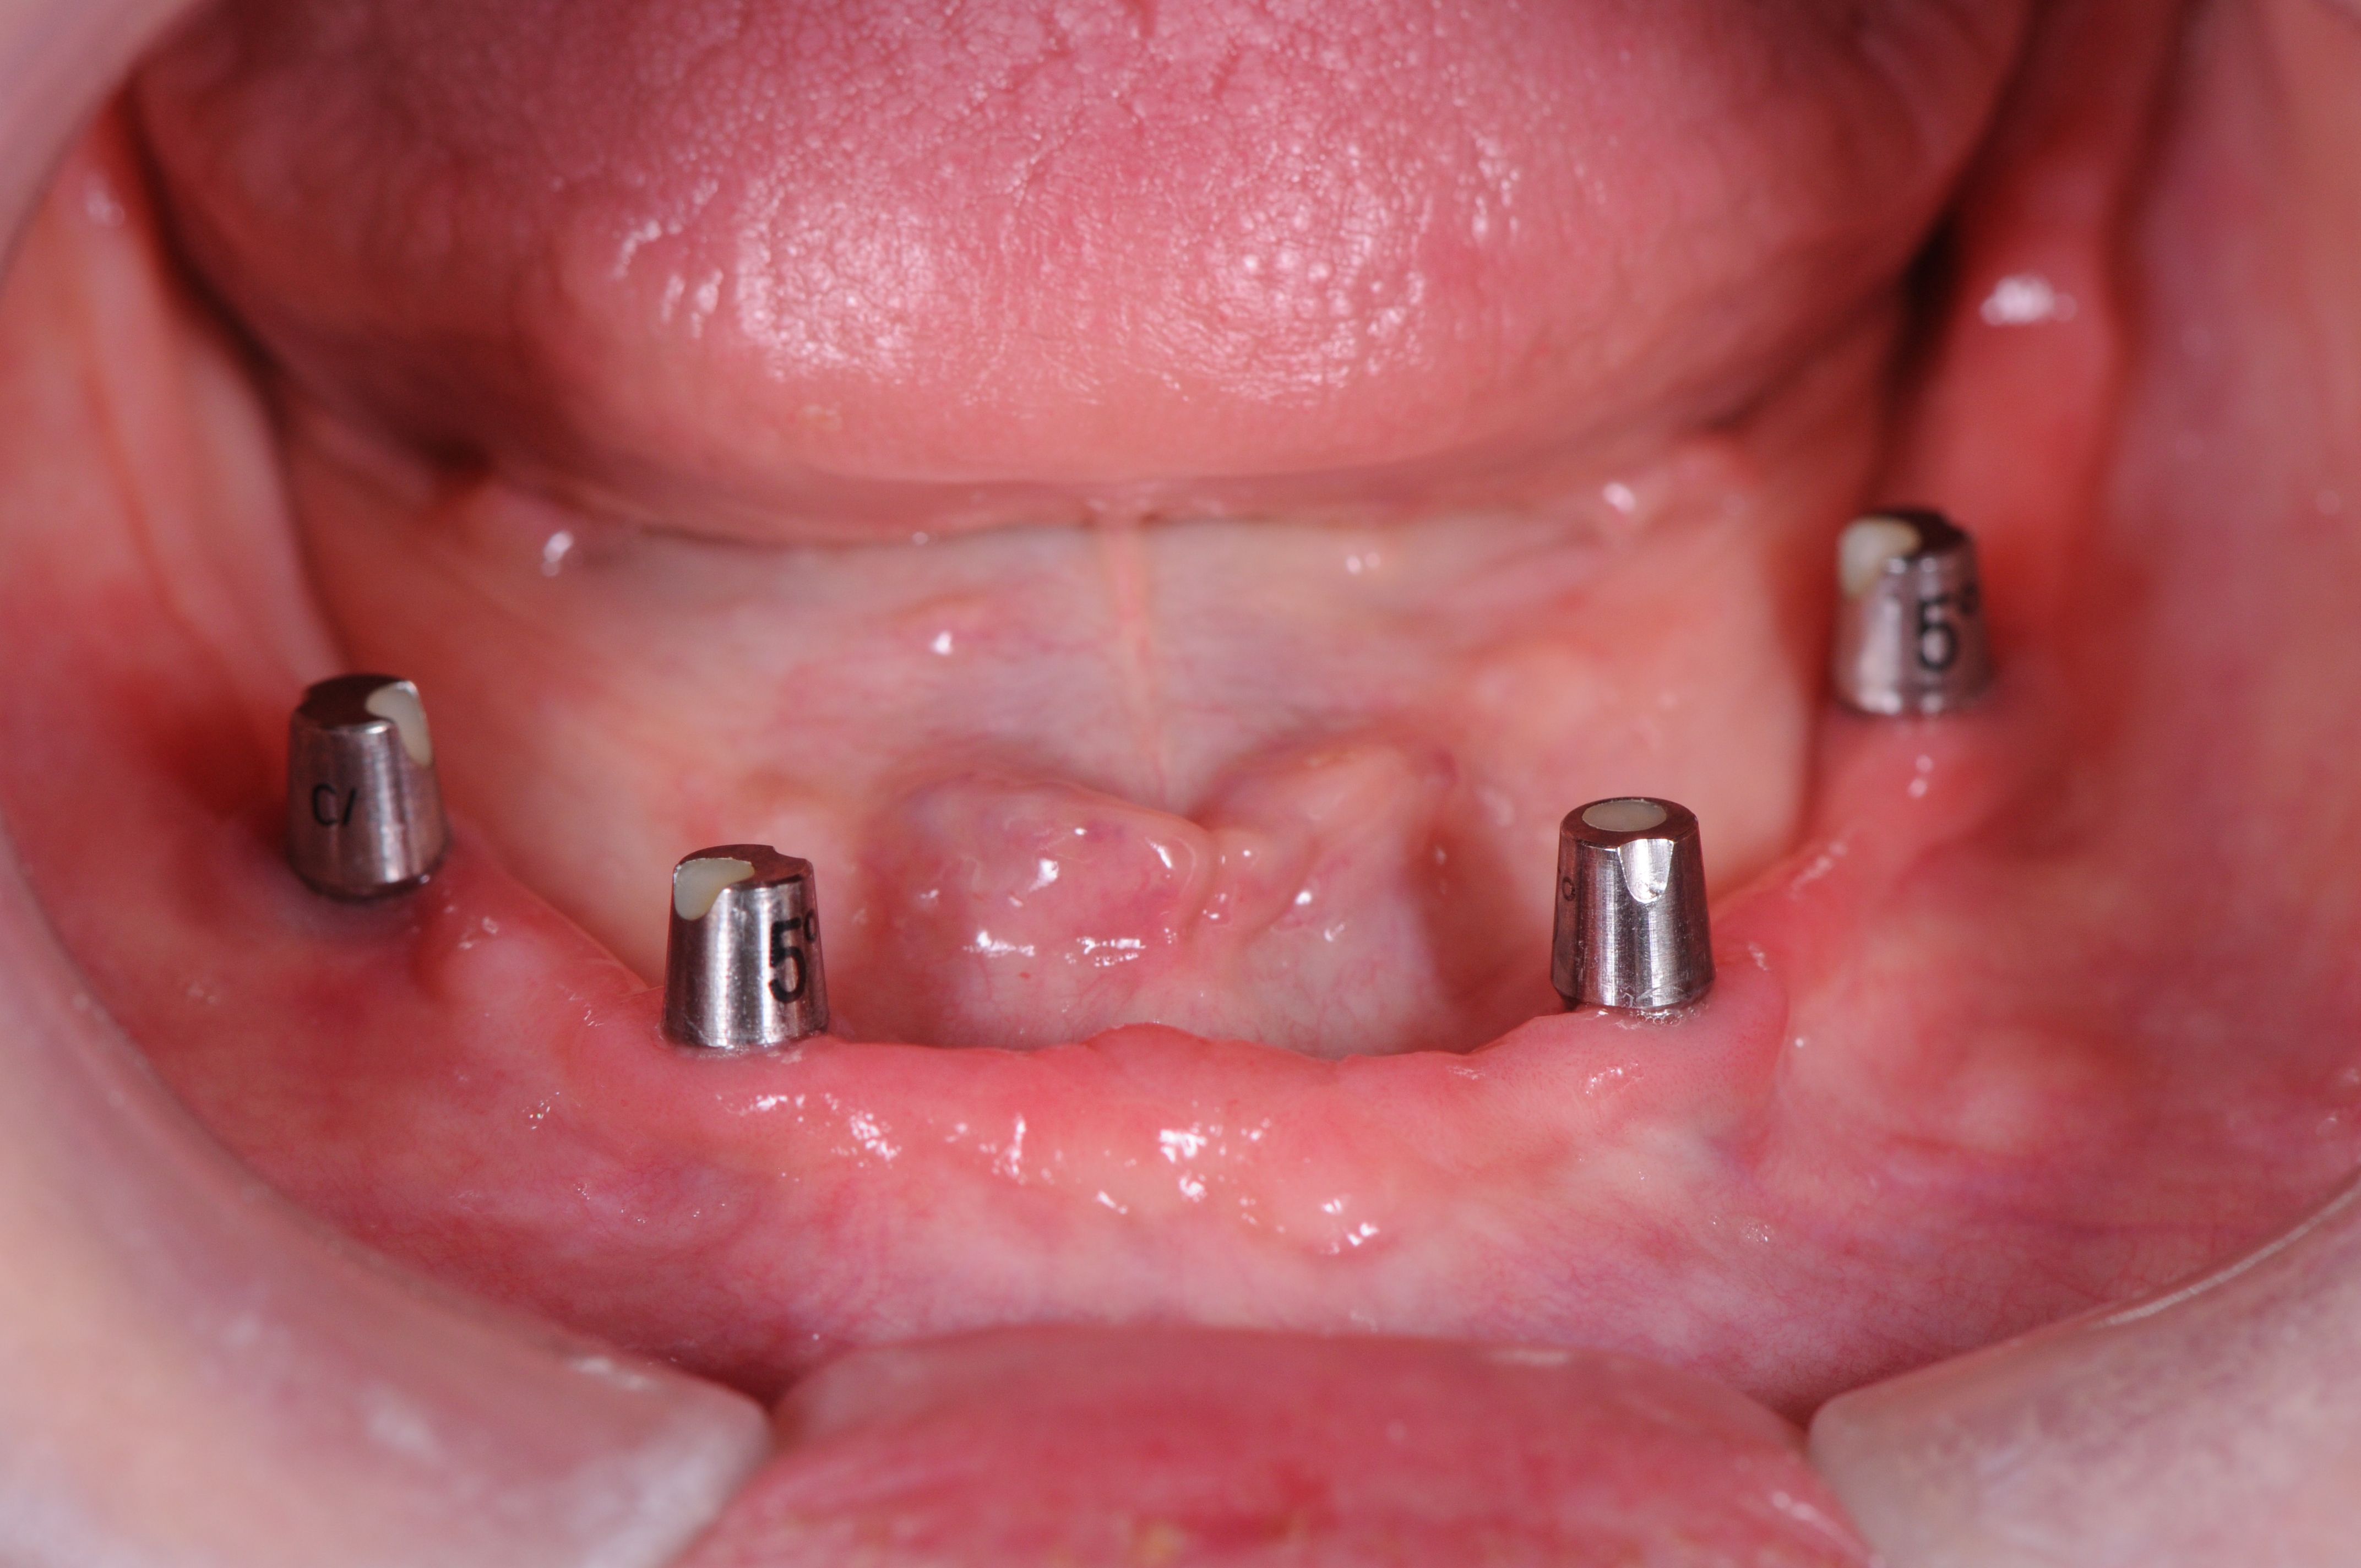

This photo shows only the lower arch. Her teeth have been replaced with four implants, and small, conical-shaped attachments were connected to the implants. These small attachments are only visible when the bridge is removed (so normally they cannot be seen or felt) and are simple to clean each day.